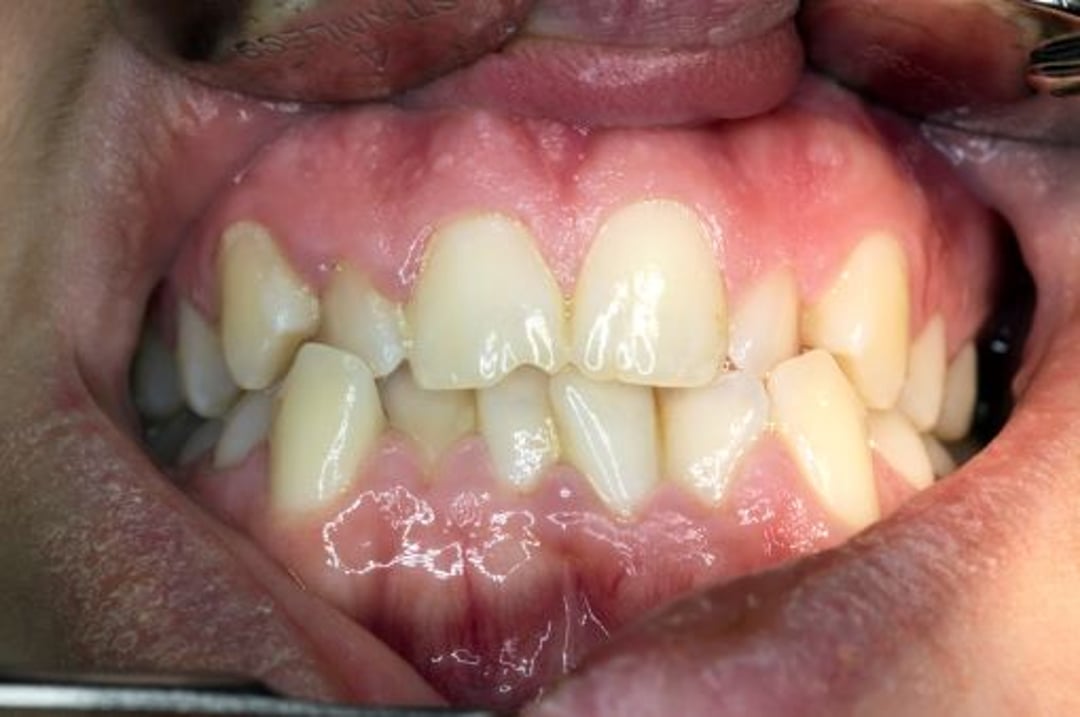

Fehlbiss bezieht sich auf die Stellung der Zähne und die Art und Weise, wie Ober- und Unterkiefer zusammenpassen.

Im Idealfall greifen die vorderen Oberkieferzähne leicht über die des Unterkiefers. Diese Überlappung ermöglicht es den Höckern des jeweiligen Zahns, sich in die entsprechende Vertiefung des gegenüberliegenden Zahns zu fügen. Die richtige Ausrichtung bewirkt den wirksamsten Kauvorgang und die gleichmäßige Kraftverteilung beim Kauen. Beim Kauen wirkt eine Kraft von über 1000 Kilopascal auf die Backenzähne und beim Zusammenbeißen der Zähne im Schlaf eine Kraft von 1700 Kilopascal. Wenn durch eine Zahnfehlstellung die Kräfte ungleich verteilt sind, können sich die Zähne ungleichmäßig abnutzen, Teile der Zahnkrone können brechen, und die Zähne können sich schließlich lockern.